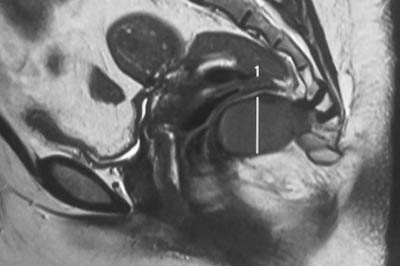

Disc prolapse

disc-prolapse

Disc is a cushion like strecture lying between the vertebral bones.Jelly like substance within the disc is responsible for the flexibility of back bone...

Disc is a cushion like strecture lying between the vertebral bones. Jelly like substance within the disc(Nucleus pulposus) is responsible for the flexibility of back bone. Some times the jelly like substance comes out of its boundary and is called as disc prolapse .

disc-prolapse-intro

Disc prolapse if occurs in the neck it causes neck pain with arm pain. If it occurs in low back it causes lowback pain with leg pain.Pt might also have weakness and numbness of arm or leg depending upon the severity of nerve compression.

Xray is the first investigation needed. MRI may be needed if pain or weakness is severe.

Mostly pain will subside with physiotherapy , rest and pain medications. Discectomy surgery might be needed if pt has persistent arm or leg .